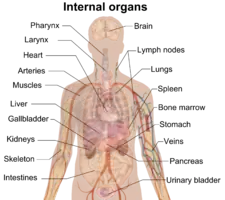

Author: Mikael Häggström

This is a gallery of medical images contributed by Mikael Häggström by 2014. Full text | Download doi: 10.15347/WJM/2014.008

Author: David Richfield

This is a gallery of images contributed to Wikimedia projects by David Richfield by 2014 Full text | Download doi: 10.15347/WJM/2014.009

Author: Blausen.com staff

This is a gallery of images contributed to Wikimedia projects by Blausen Medical by 2014. Full text | Download doi: 10.15347/WJM/2014.010